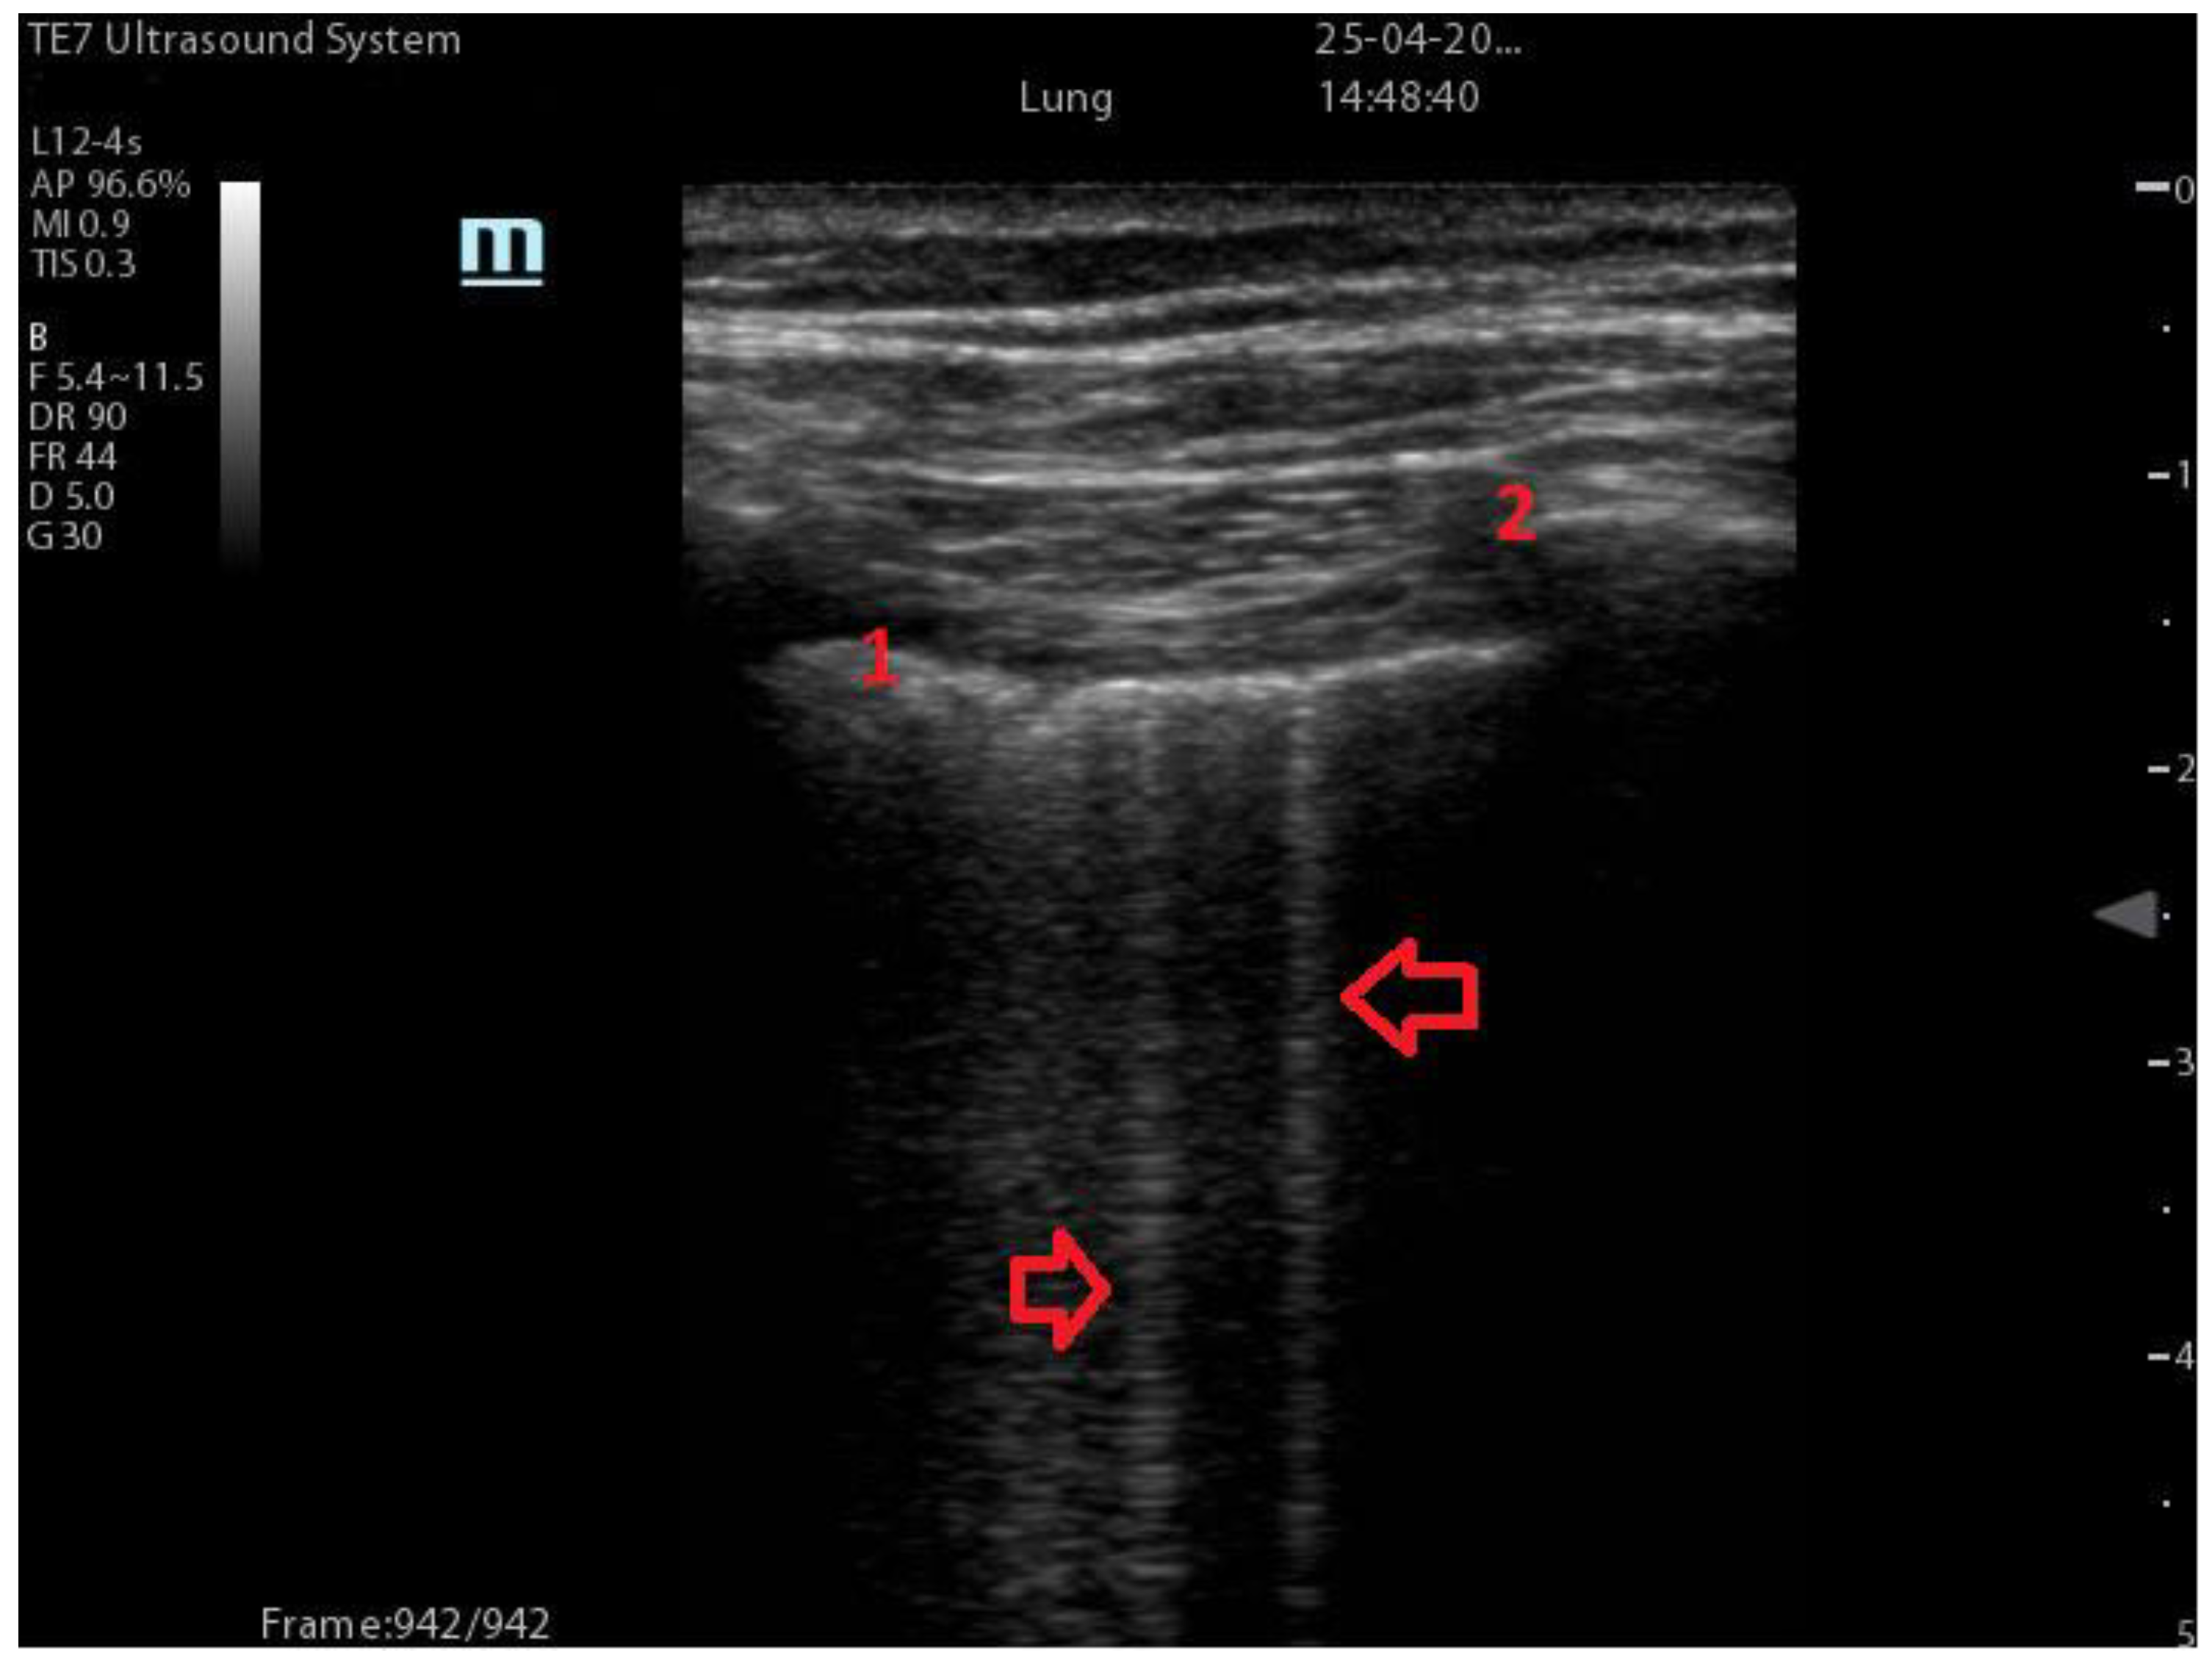

| Integrated ultrasound score (I-LUS) [41] | 0: A-lines or ≤2 B-lines plus regular sliding 1: ≥3 B lines or spaced focal points plus regular sliding 2: coalescing B-lines 3: pulmonary consolidations Plus: Presence of pleural effusion (1: present, 0: absent). Presence of pericardial effusion (1: present, 0: absent). Measurement of the IVC respiratory variation (<0–33%) (1: present, 0: absent). Diaphragm excursion: measured in normal respiration, with M-mode through a right subcostal scan. A value > 2 +/− 0.5 cm is considered normal (0 points), while an inferior value is considered abnormal (1 point). | ![]() 12 AREAS |